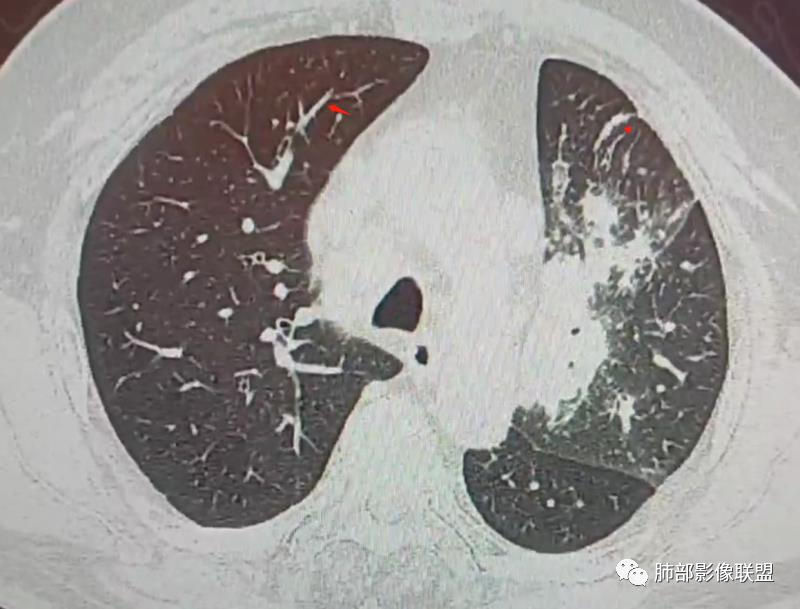

南边:这些是中轴间质增厚?树芽征?

Coke with ice:潘老师,这里是小叶间隔吧?串珠样的。

南边:是的。

南边:尖后段弥漫小叶间隔,中轴间质增厚,部分有结节感,大家考虑啥。

Coke with ice:我觉得是典型的癌淋,较大范围的,比如叶分布,甚至是整个单侧肺,单侧的肺小叶间隔增厚,极大概率是癌淋,另外一个疾病谱就是负压性肺水肿。

PLC的主要CT征像当中肺纹理异常改变最常见,肺纹理不规则增多、增粗并多发微小结节状更形象解释癌细胞在淋巴管内生长成结节及周围间质增生,导致淋巴管通道堵塞,远处淋巴液回流受阻,通过其它细小交通回流,从而导致肺纹理增粗增多,是PLC较有特征性CT征象,其它疾病所导致的肺纹理增多增粗一般较规则,可为粗细不均或受牵拉变形却极少出现结节状增粗并呈串珠状排列。小叶间隔不规则增厚并多发小结节也是因为小叶间隔淋巴管癌细胞生长及淋巴管通道受阻扩张所致,虽然小叶间隔结节状增粗,但小叶结构不变形是PLC较为特征的CT表现,肺纤维化、 肺水肿、肺胶原病及结节病等肺间质性病变中较少见小叶间隔结节状增粗,而且它们一般导致肺小叶结构变形。肺小叶内间质增生及(或)核心小结节无明显特异性,其表现与特发性肺纤维化、 尘肺及结缔组织病及其它可导致肺间质性纤维化疾病的小叶内间质增厚相类似。PLC导致的胸膜增厚也有一定特征,一般累及胸膜范围较广,程度轻,密度较淡, 部分呈花边样改变,以叶间胸膜较常见,绝大部分病例叶间胸膜受累呈轻度增厚并沿表面排列多发微小结节,伴随PLC其它征象,未见单独存在。肺内结节及 (或)小斑片状实变影无特异性, 与肺结核、炎症、肺血行转移瘤及类风湿等结缔组织病的肺部表现相似,也可能为合并血行转移及肺部感染。纵膈及肺门淋巴结肿大、胸腔及心包积液均无特异性,曾有文献报道,单侧叶间裂积液对PLC的诊断有相对特异性, 因单侧的叶间裂积液主要是由于胸膜下淋巴管堵塞,淋巴回流受 阻所致,可提示PLC的存在。

综合上述,肺纹理不规则增粗并多发微小结节、肺小叶间隔不规则增厚并多发微小结节、轻度增厚的胸膜并多发微小结节对诊断PLC具有重要意义,三者征像同时存在时,结合肿瘤病史及临床症状, 基本可以明确诊断PLC。